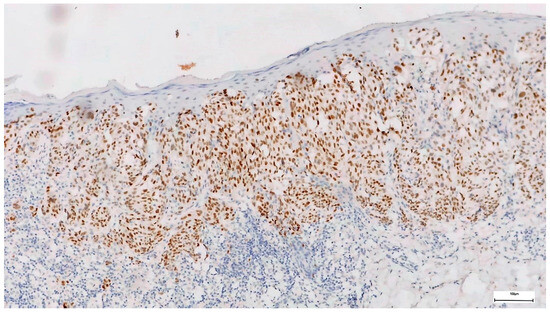

- Gassenmaier, M.; Hahn, M.; Metzler, G.; Bauer, J.; Yazdi, A.S.; Keim, U.; Garbe, C.; Wagner, N.B.; Forchhammer, S. Diffuse Prame Expression Is Highly Specific for Thin Melanomas in the Distinction from Severely Dysplastic Nevi but Does Not Distinguish Metastasizing from Non-Metastasizing Thin Melanomas. Cancers 2021, 13, 3864. [Google Scholar] [CrossRef]